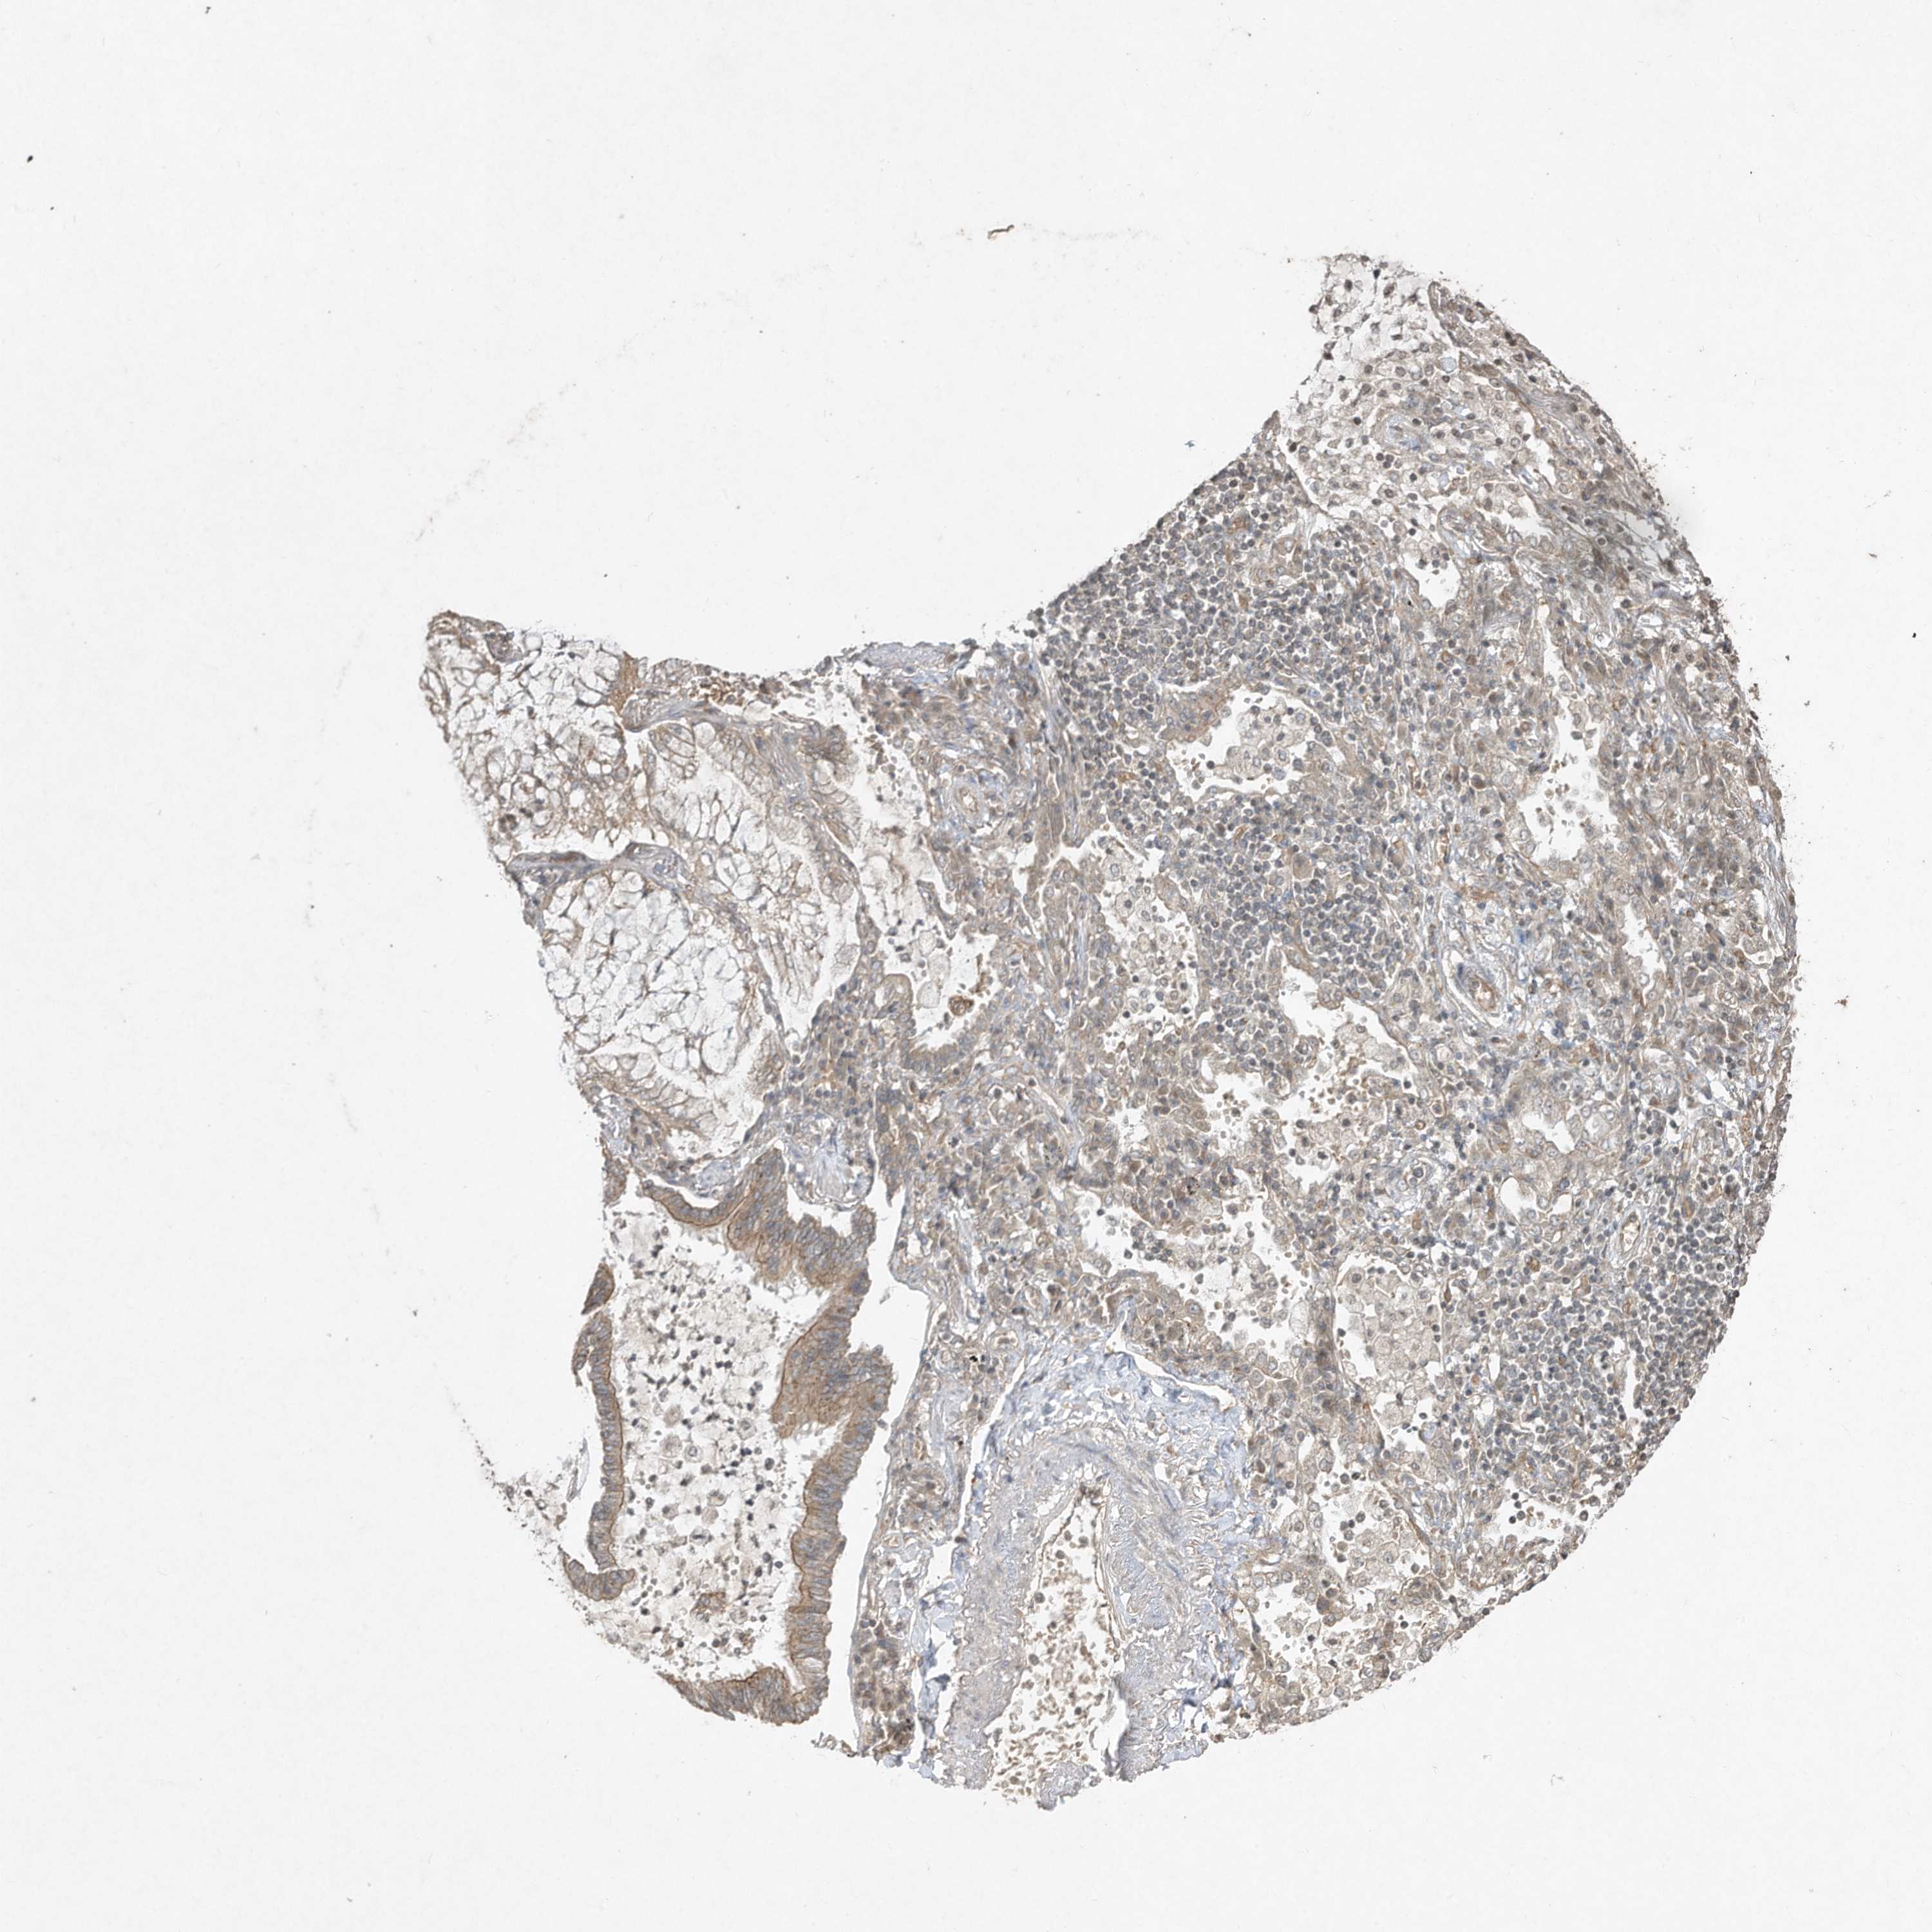

LUNG ADENOCARCINOMA (VALIDATION) - Interactive survival scatter ploti

MATN2 is not prognostic in Lung Adenocarcinoma (validation)

: 6.06

Average pTPM 13.0

Number of samples 105